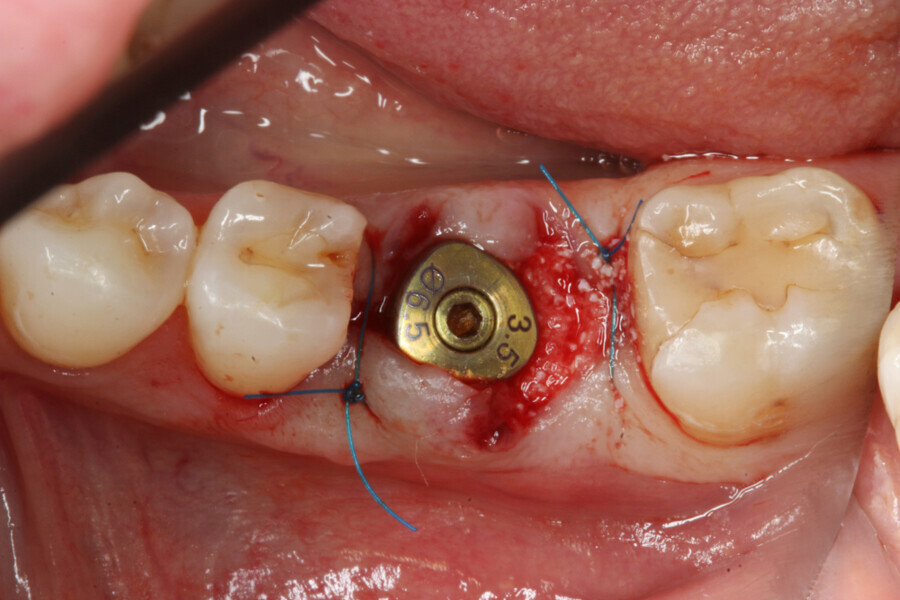

The implant site was prepared following the recommended drilling protocol for the planned PrimeTaper EV 4.2 mm diameter implant (drills #1, 3 and 4; Fig. 2). After cortical preparation with drill #5, the implant was placed. The preparation was finalised with a tap, owing to dense trabecular bone (Fig. 3). The implant was inserted to a torque of 42 Ncm (Fig. 4).

Immediately after implant placement (Fig. 5), the abutment position was registered with an intra-oral scan using Primescan (Dentsply Sirona; Fig. 6). At the end of the surgical procedure, the socket was grafted with Symbios (Dentsply Sirona) and a healing abutment was seated (Fig. 7). Radiographic evaluation was performed on the same day (Fig. 8). On basis of an intra-oral scan, an Atlantis abutment and Atlantis provisional crown were designed and fabricated with an Atlantis IO FLO (Fig. 9).